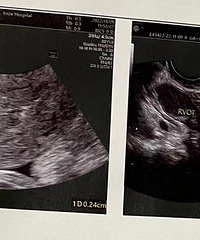

预产期:2023年5月20日建卡医院:温岭市妇幼保健院产检医院:温岭市妇幼保健院胎宝宝小名:还没取呢生产医院:未定哦B超照片/孕期相关照片一张